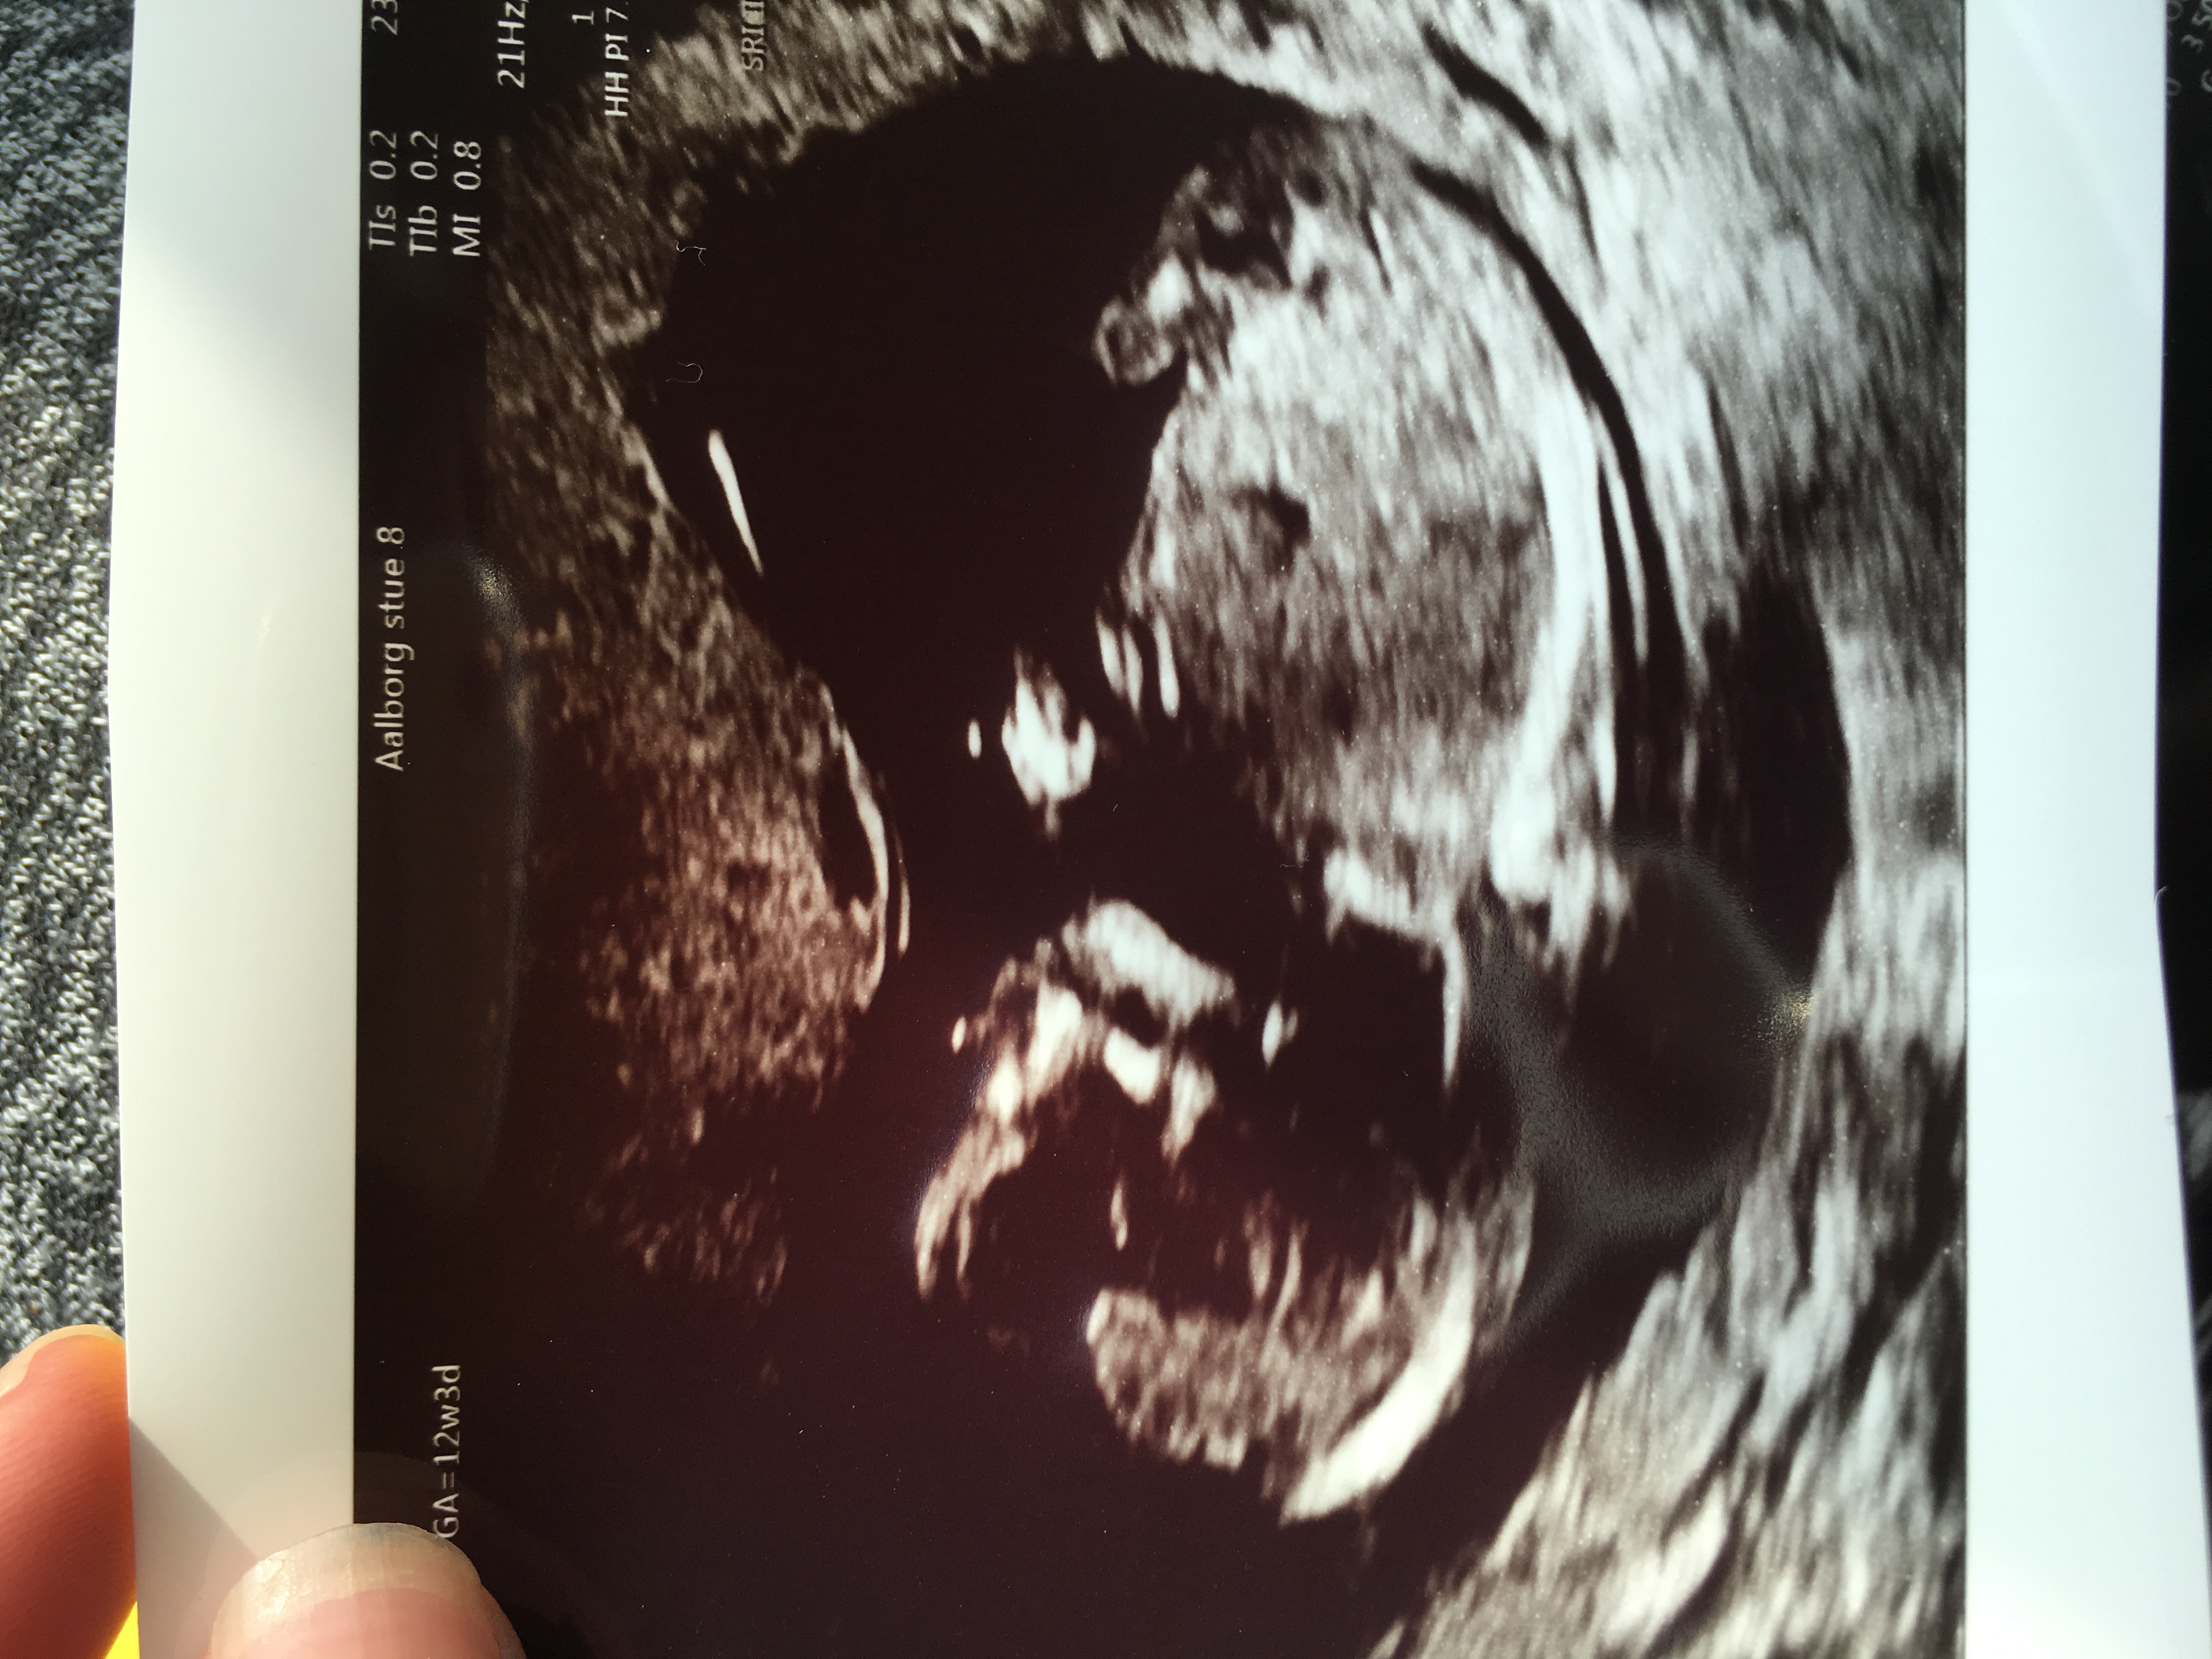

Girl or boy? I'm not sure .. anyone who will guess

Think girl if late 12 weeks gestation onwards x

Maybe girl

girl

I would be leaning towards girl